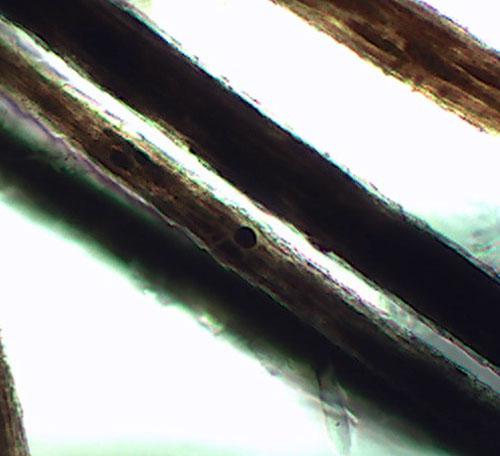

En revanche trichogramme montre des lésions pilaires : les poils sont déformés (dysplasie pilaire) et des agrégats de mélanine de forme irrégulière sont présent dans le cortex et la médulla des poils (photos 4)

Photos 4a et 4b : Observation microscopique (x400) d’une trichoscopie: noter les agrégats de mélanine.